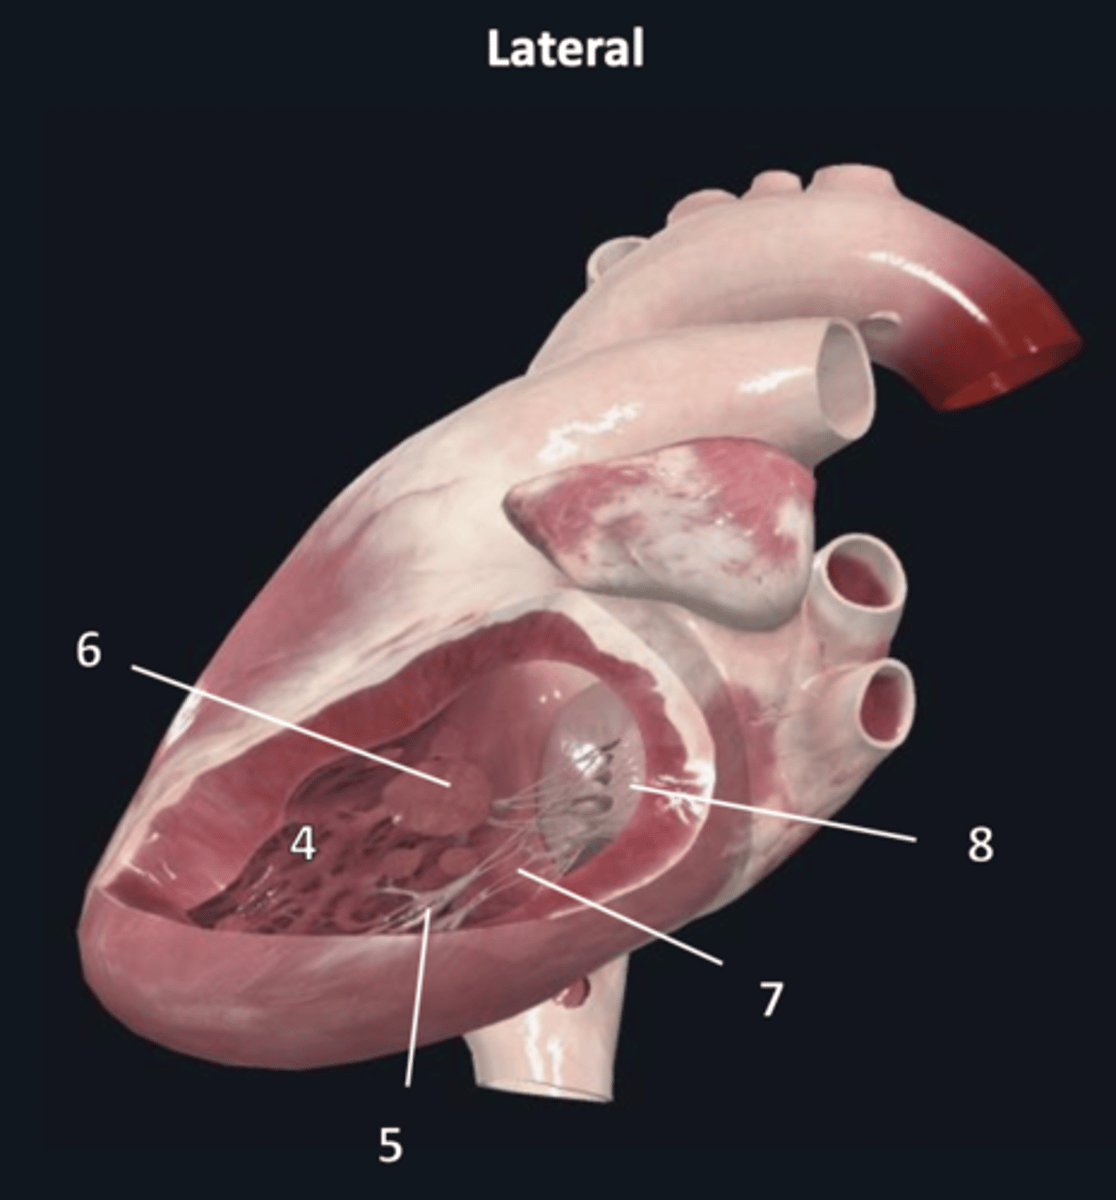

left atrium

1

left auricle

2

left ventricle

3

trabeculae carneae

4

inferior papillary muscle

5

superior papillary muscle

6

chordae tendineae

7

left atrioventricular valve

8 (opening)

aortic semilunar valve

9 (opening)